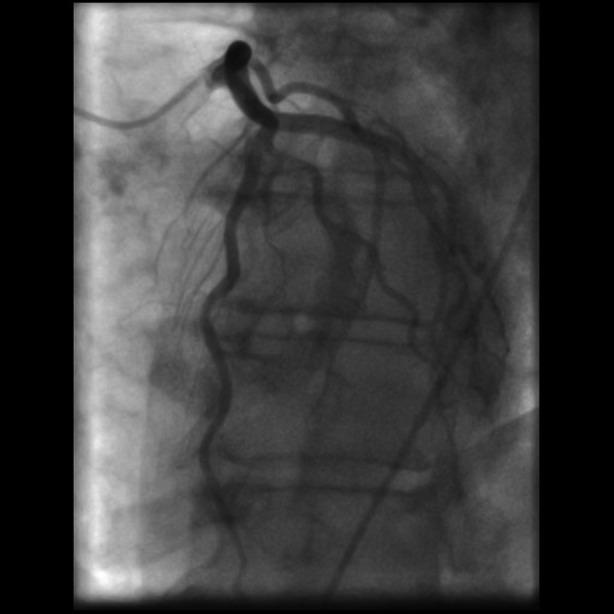

An 82-year-old woman with severe aortic valve stenosis (AS) and a significant proximal right coronary artery (RCA) stenosis presented with decompensated heart failure and acute kidney injury. She was treated with intravascular ultrasound (IVUS)-guided percutaneous coronary intervention (PCI) and trans-oesophageal echocardiography (TOE)-guided transcatheter aortic valve replacement (TAVR).

一名82岁女性,患有严重主动脉瓣狭窄(AS)且右冠状动脉(RCA)近端存在明显狭窄,出现失代偿性心力衰竭和急性肾损伤。她接受了血管内超声(IVUS)引导下的经皮冠状动脉介入治疗(PCI)以及经食管超声心动图(TOE)引导下的经导管主动脉瓣置换术(TAVR)。